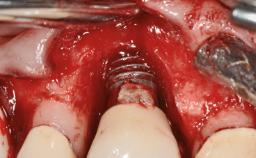

A 77-year-old male patient was referred for the management of frequent and repeated acrylic fracture of his existing mandibular fixed full-arch implant-supported metal/acrylic prosthesis. He also complained about softtissue soreness and the lack of retention and stability of his maxillary removable partial metal/acrylic prosthesis. Both prostheses had been delivered two years previously as part of his full-mouth rehabilitation (caries, tooth wear, tooth fracture). His medical history revealed high blood pressure, controlled with the use of antihypertensive medication.